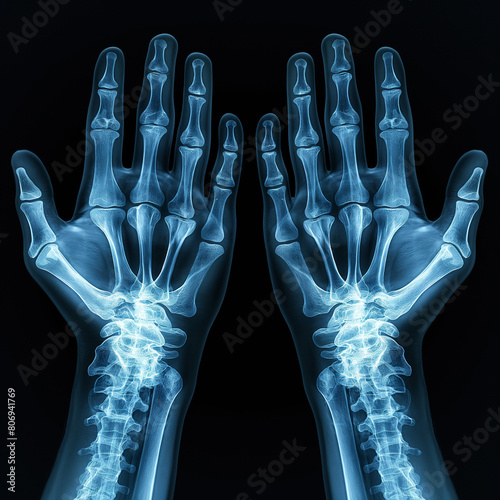

Enchondroma Hand

Enchondroma - Azouz Hand SurgeryAzouz Hand Surgery Enchondromas - Pathology - Orthobullets LearningRadiology- Enchondroma Enchondroma-of-hand LearningRadiology- Enchondroma Enchondroma Hand